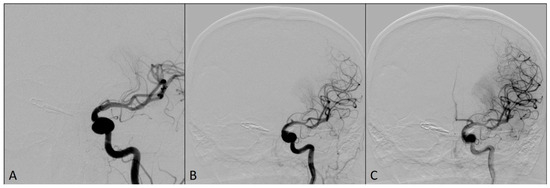

2. Case Report